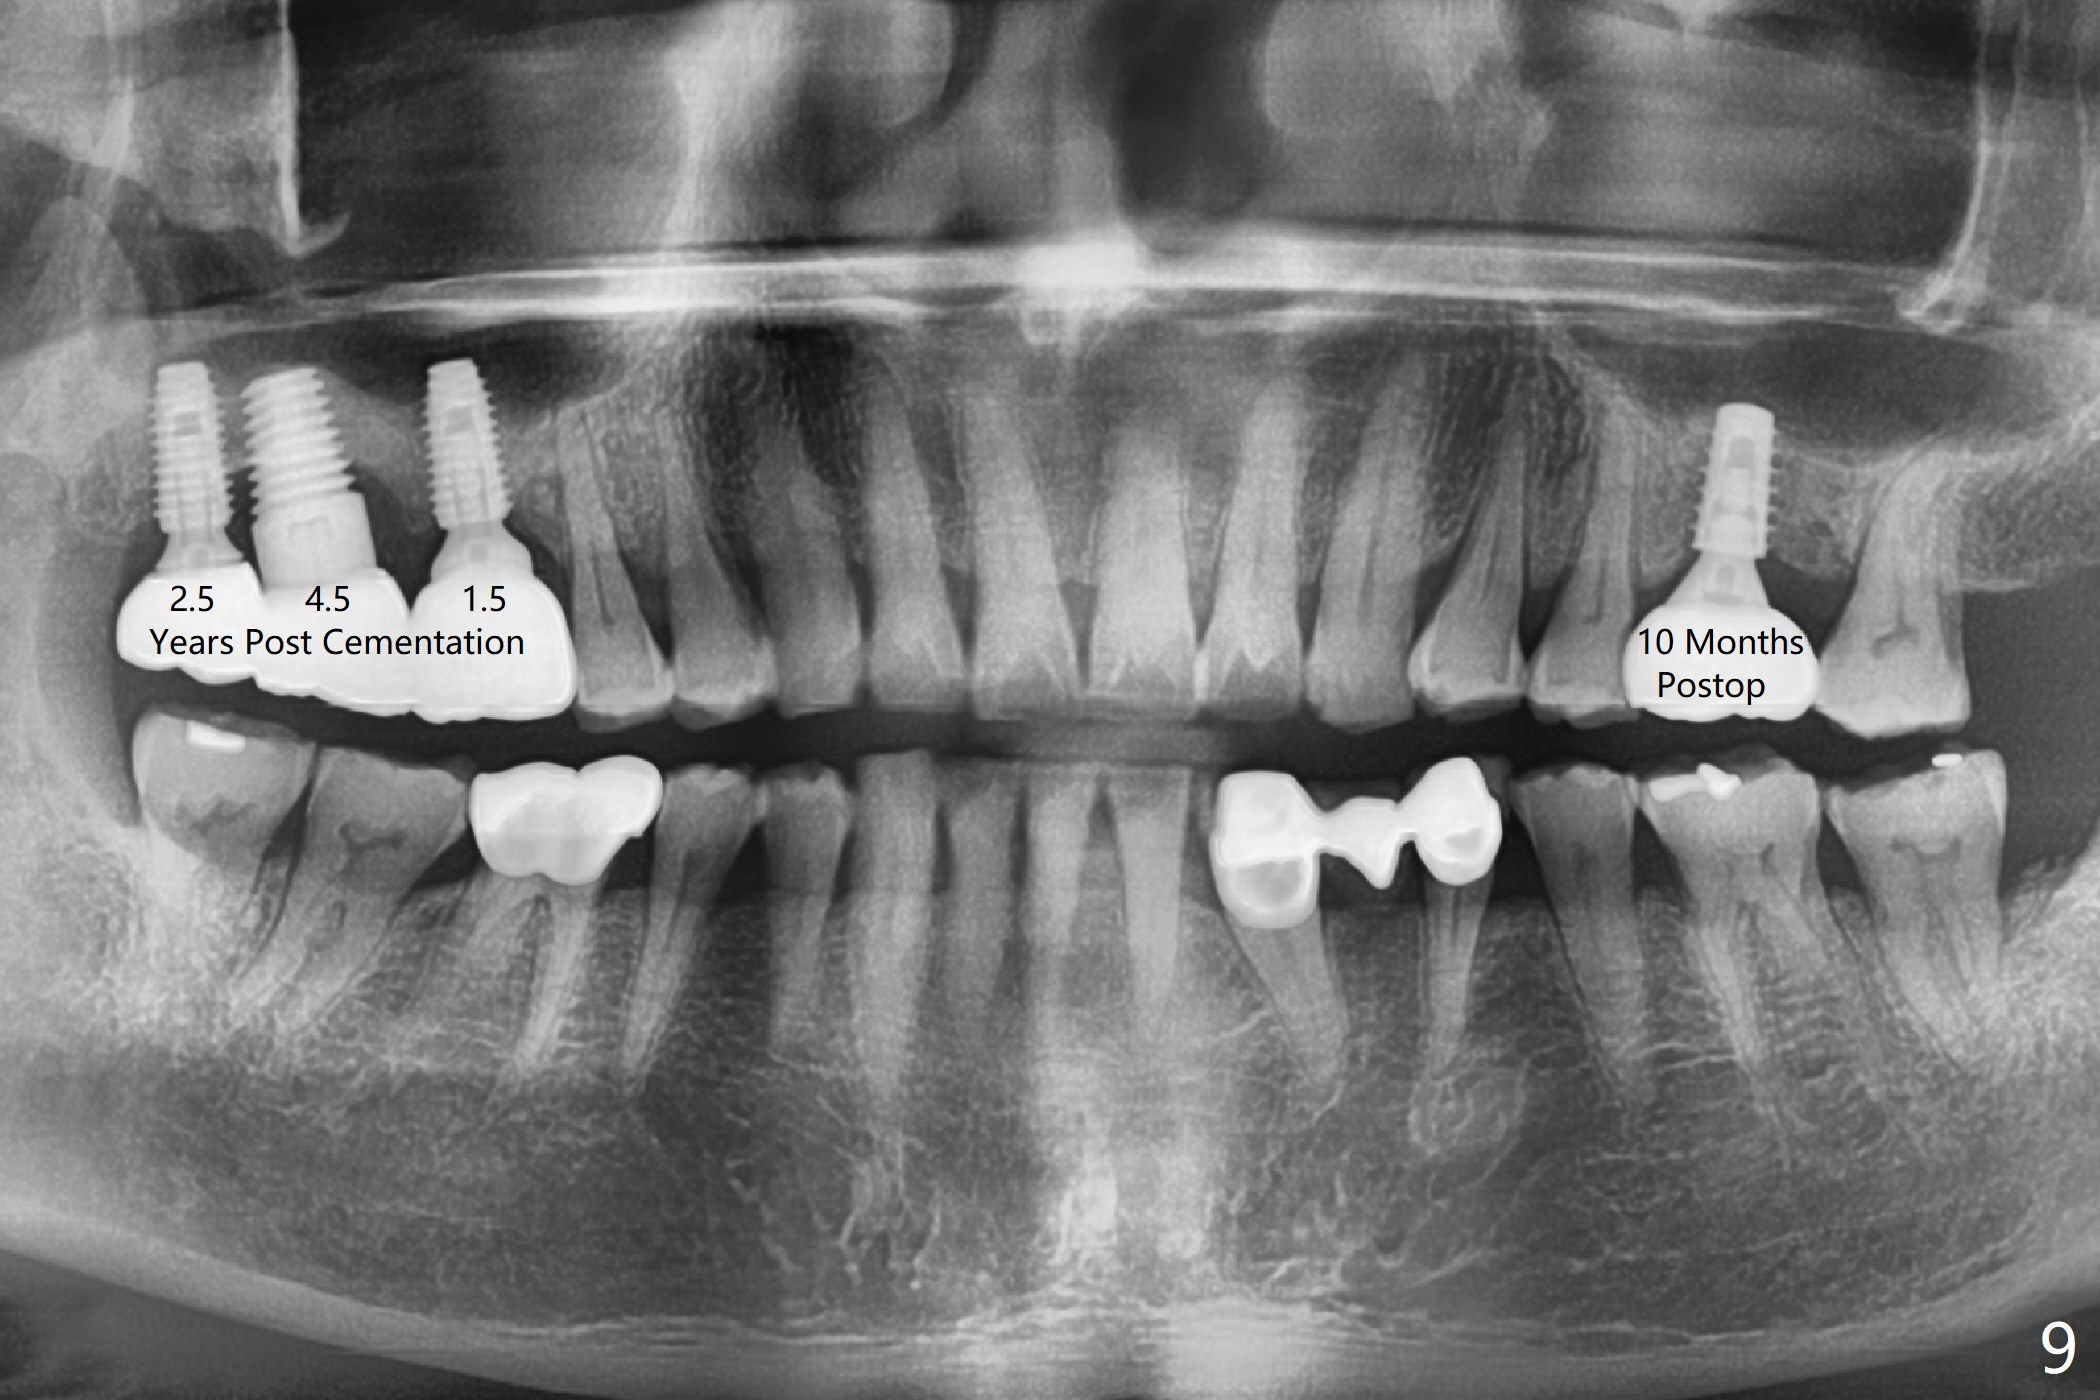

After extraction of the tooth #14 with palatal root fracture (Fig.1 <), sinus membrane perforation is found in the buccal wall of the palatal socket (Fig.2 ^). Osteotomy is initiated in the buccal strut of the septum (Fig.3 *). As the osteotomy increases in diameter, it slides into the mesiobuccal socket (Fig.4). A 5x9 mm implant is placed slightly mesial; after placement of a 6.5x4(2) mm abutment and insertion of collagen plug in the palatal socket, Vera graft is placed in the remaining socket space (Fig.5 *). Nasal hemorrhage persists 1.5 months postop (Fig.6). The distal gingiva is slightly tender and erythematous; a 6x4 mm healing abutment is placed 2.5 months postop (Fig.7,8). Impression is taken after laser gingivectomy 3.5 months postop. The patient feels discomfort at the site 7 days post impression, although the gingiva heals after laser treatment. Two weeks after cementation, the mesial gingiva is mildly tender and the abutment screw is loose. A 6x3 mm healing abutment is placed. The abutment/crown is reseated 10 months postop (Fig.9).